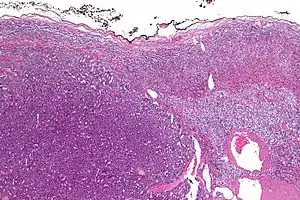

| Micrograph of an adrenocortical carcinoma (left of image – dark blue) and the adrenal cortex it arose from (right-top of image – pink/light blue). Benign adrenal medulla is present (right-middle of image – gray/blue). H&E stain. | |

Adrenal tumors are often not biopsied prior to surgery, so diagnosis is confirmed on examination of the surgical specimen by a pathologist. Grossly, ACCs are often large, with a tan-yellow cut surface, and areas of hemorrhage and necrosis. On microscopic examination, the tumor usually displays sheets of atypical cells with some resemblance to the cells of the normal adrenal cortex. The presence of invasion and mitotic activity help differentiate small cancers from adrenocortical adenomas.[6] Several relatively rare variants of ACC include: